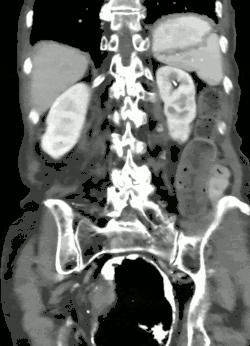

Bei Erwachsenen wird häufig beim Bild eines akuten Abdomens auch die Computertomographie eingesetzt. Als typisches Zeichen neben der massiven Überblähung beim Volvulus kann hiermit auch die Drehung der Mesenterialwurzel mit ihren Gefäßen (Whirlpool-Zeichen) gezeigt werden.